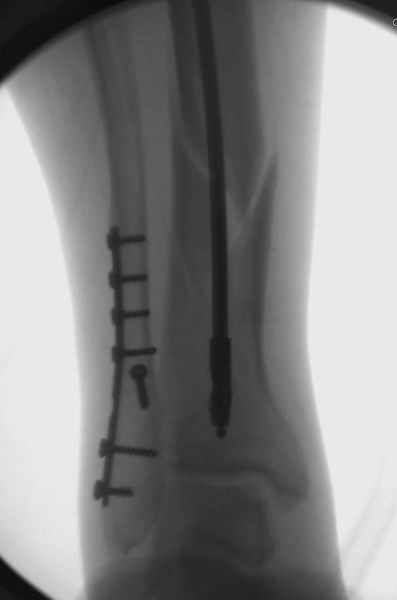

спрашивает что делать с больным который поступил недавно, фермер 55 лет падение при пьяной драке в баре, года два назад перенес операцию на лодыжке, на снимках и КТ перелом без вовлечения сустава,

Здесь мы использовали новый Synthes Nail с дополнительными дырками, в проксимальной части 4: по две косых и поперечные (один стандартный а другой динамический), в дистальной части две поперечные, прямая и косая. Вес больного более 120 кг, нагрузку начнем через месяц.

Получилось красиво, поздравляю. Вверху можно было ограничиться одним винтом во фронтальное статическое отверстие, зачем два 45-градусных?

При такий спирали задний край tibia может быть сломан - нет ли этого в данном случае? На всякий случай можно было ввести 1-2 винта 4,5 мм спереди назад мимо гвоздя. Хотя самый дистальный блокирующий винт, возможно, зацепил этот отломок. А какой тут диаметр гвоздя и locking винтов?